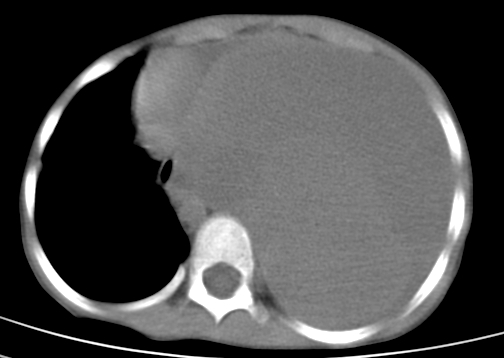

患儿 女 4岁,发热 咳嗽 胸透 考虑:左侧脓胸

左侧胸廓内见大量密实阴影,肺尖部尚有少量肺组织影,纵膈明显受压移位,肋骨未见明显受侵征象,虽然病人年龄较小,但如此大量的“积液”,还是要警惕,不同意一般感染,可结合穿刺脱落细胞学检查。

1)考虑左肺炎症感染。2)左侧大量胸腔积液。

1)考虑左肺炎症感染。2)未经穿刺只能定左侧大量胸腔积液。

左侧张力性大量胸腔积液压迫性肺不张、感染;建议治疗后复查。